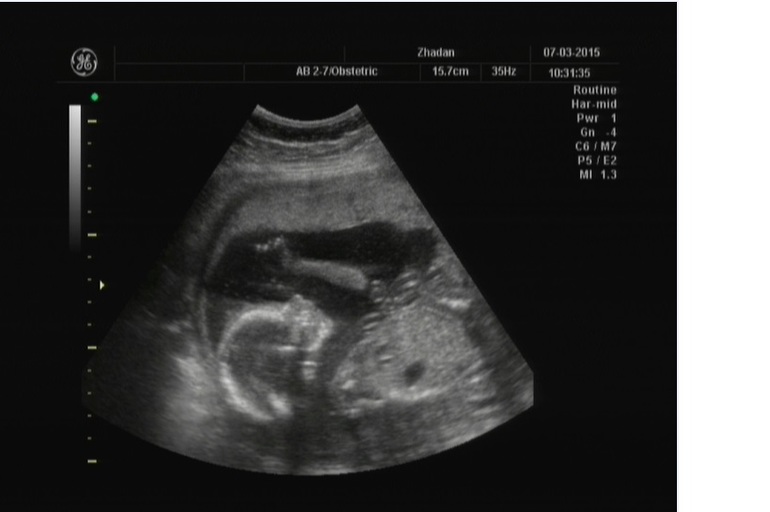

Был вчера)))) Волновалась жутко))))))) но все хорошо, весим 295 г, рост 20 см))))))) все в порядке))))))) Пальчик сосали, носик чесали и никого не стеснялись))))))

Как я и писала все были настроены на мальчишку)))))) на первом скрининге сказали - мальчик))))))...что в принципе подтверждало традиции моей семьи)) У бабули первая дочь (моя мама) второй сын))) у мамы первая я, второй брат....потому результат первого узи никого не удивил...Макс сиял аки сонечко)))))))).......вобщем, как Вы уже поняли ничто не предвещало))))))) Правда были у меня сомнения-таки.....уж очень беременности схожи......